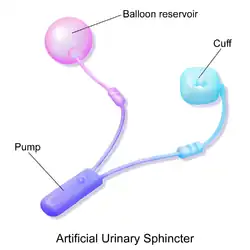

- The artificial urinary sphincter with a balloon reservoir (3-component): cuff, pump and balloon. The cuff is placed around the urethra; the pump is inserted in the scrotum and the balloon reservoir is implanted in the retropubic space – between bladder and iliac vein. The pressure in the hydraulic circuit is generated by the elastic balloon reservoir and from retropubic pressure.[1][2]

The common theme among currently available designs is a mechanical constriction mechanism – an inflatable cuff filled with sterile saline solution and placed around the urethra which keeps the urethral lumen closed; this is due to the pressure produced inside the device and an externally accessible control pump mechanism placed between two skin layers of the scrotum (subdartos pouch) which allows the user to manually relieve the constriction to allow urination.